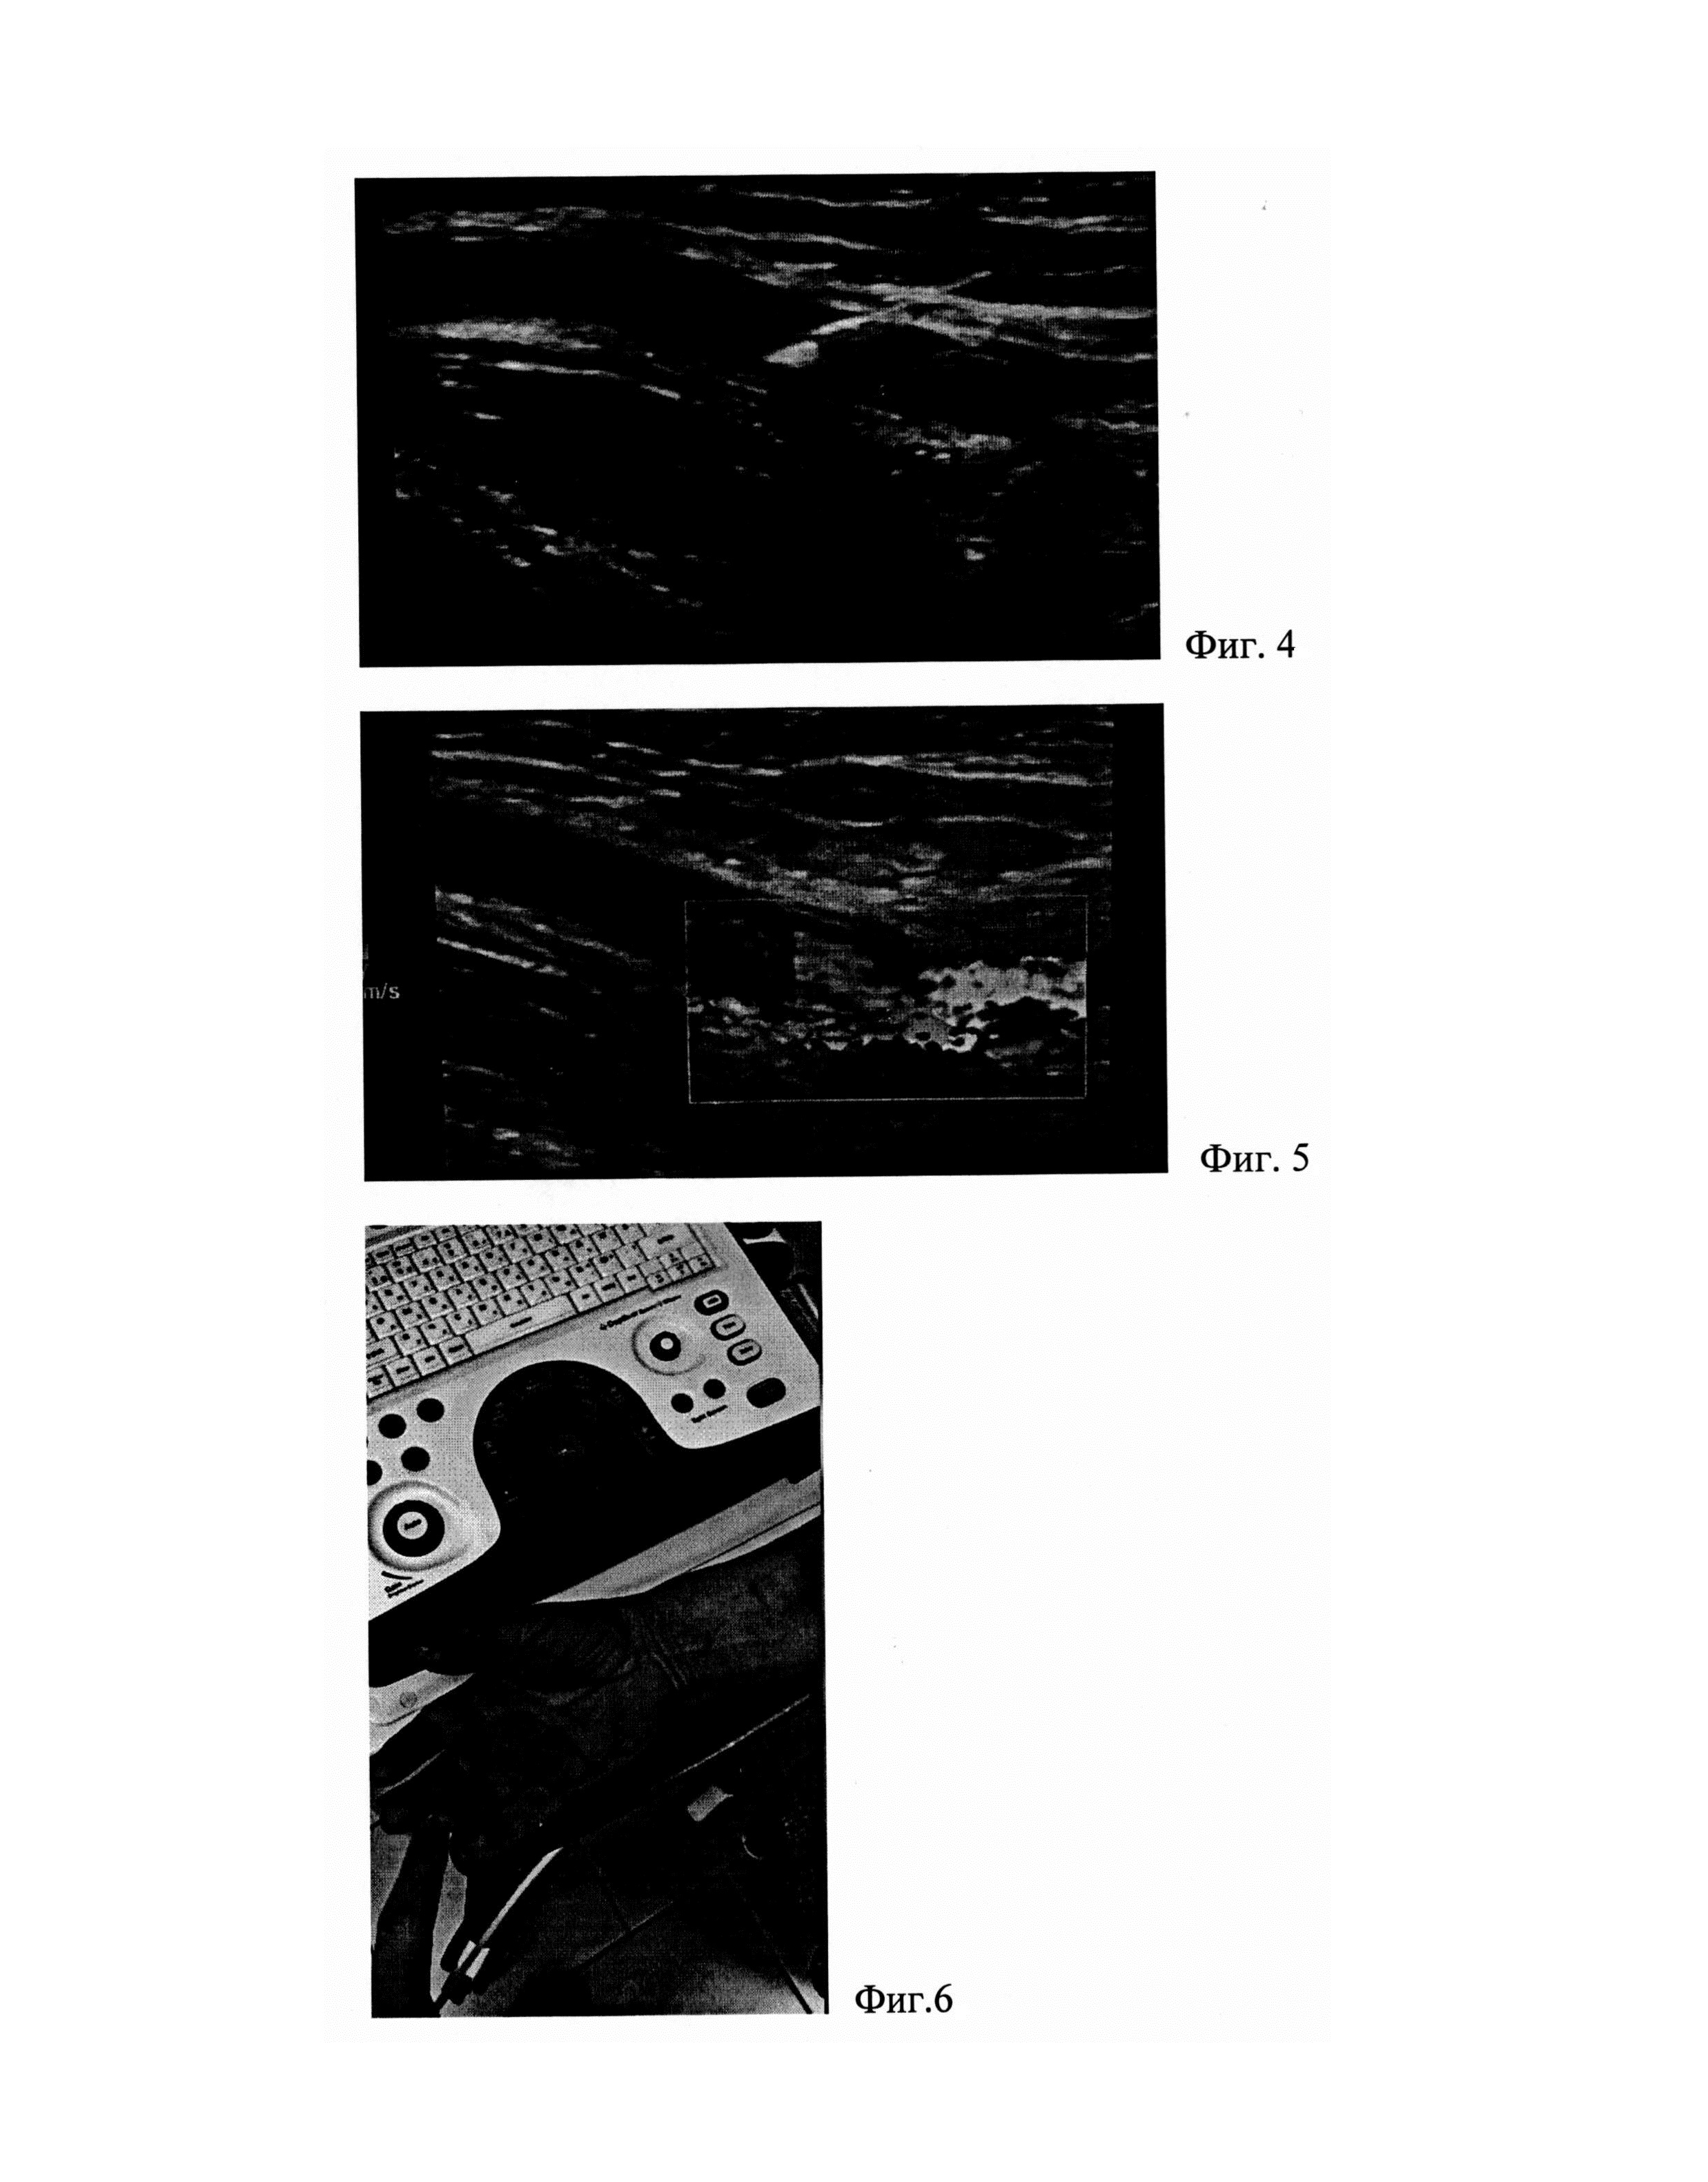

Способ поясняют приведенные иллюстрации.

[45]

Фиг. 1 - Фиг. 5 иллюстрируют клинический пример 1, где:

[46]

На фиг. 1 - фото верхней конечности при поступлении;

[47]

На фиг. 2 - результат ультразвукового сканирования: тромботические массы в просвете артерии;

[48]

На фиг. 3 - внутриартериальная инъекция препарата под ультразвуковой навигацией;

[49]

На фиг. 4 - ультразвуковое сканирование: пункционная игла в просвете артерии;

[50]

На фиг. 5 - ультразвуковое сканирование: восстановление магистрального кровотока в плечевой артерии;

[51]

На фиг. 6 - вид кисти после окончания инъекционного тромболизиса.

[62]

В условиях перевязочного кабинета хирургического отделения, в асептических условиях, под ультразвуковой визуализацией портативной ультразвуковой системой GE Logiq Е с линейным датчиком, пункционной иглой 23G длиной 150 мм, выполнена пункция тромбированного сегмента плечевой артерии в 3 точках, поочередно (фиг. 3). Инъекции препарата проводились без анестезии, с предварительным внутримышечным введением препарата Трамадол 2,0 мл. При каждой пункции болюсно интратромбально вводился тромболитик Актилизе, при введении производились возвратно-поступательные движения иглой, с целью расслаивания структуры тромба и равномерного его распределения, до полной инфильтрации тромба по всей протяженности (фиг. 4). После каждой пункции, и извлечения иглы, производилась умеренная компрессия места прокола артерии ультразвуковым датчиком, длительность компрессии до достижения гемостаза составляла, в среднем, 3-5 минут. Общее время процедуры инъекционного тромболизиса составило 15 минут, общая доза введенного тромболитика - 15 мг. Далее пациентка транспортирована в общехирургическую палату, где производилось ее согревание системой обогрева пациента Equator (одеяло), с заданным температурным режимом 44°С, в течение 2-х часов.

[63]

Через 2 часа пациентка отметила клиническое улучшение, проявлявшееся в уменьшении интенсивности болевого синдрома, и потеплении конечности. При контрольном ультразвуковом сканировании через 4 часа отмечена полная реканализация просвета плечевой, лучевой и локтевой артерий, с восстановлением магистрального кровотока (фиг. 5). Клинически, пациентка отмечала полный регресс симптомов острой ишемии, с купированием болевого синдрома, и восстановлением чувствительности. Кисть физиологической окраски, теплая (фиг. 6).